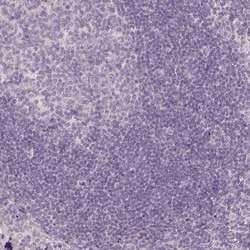

Invitrogen™ TMEM16B Polyclonal Antibody

Calcium-activated chloride channels (CaCC) are present in many cell types and mediate physiological functions such as epithelial secretion, sensory signal transduction, and smooth muscle contraction. Subunits of these CaCC's include the transmembrane proteins TMEM16A and TMEM16B. TMEM16B is predicted to have eight transmembrane domains with both the amino and carboxy termini in the cytoplasm and is expressed in several tissues including olfactory sensory neurons as well as photoreceptors in mammalian retina. Like TMEM16A, TMEM16B is thought to form at least part of CaCC's but has different biophysical characteristics such as voltage dependence and unitary conductance.

| Applications | Immunohistochemistry (Paraffin) |